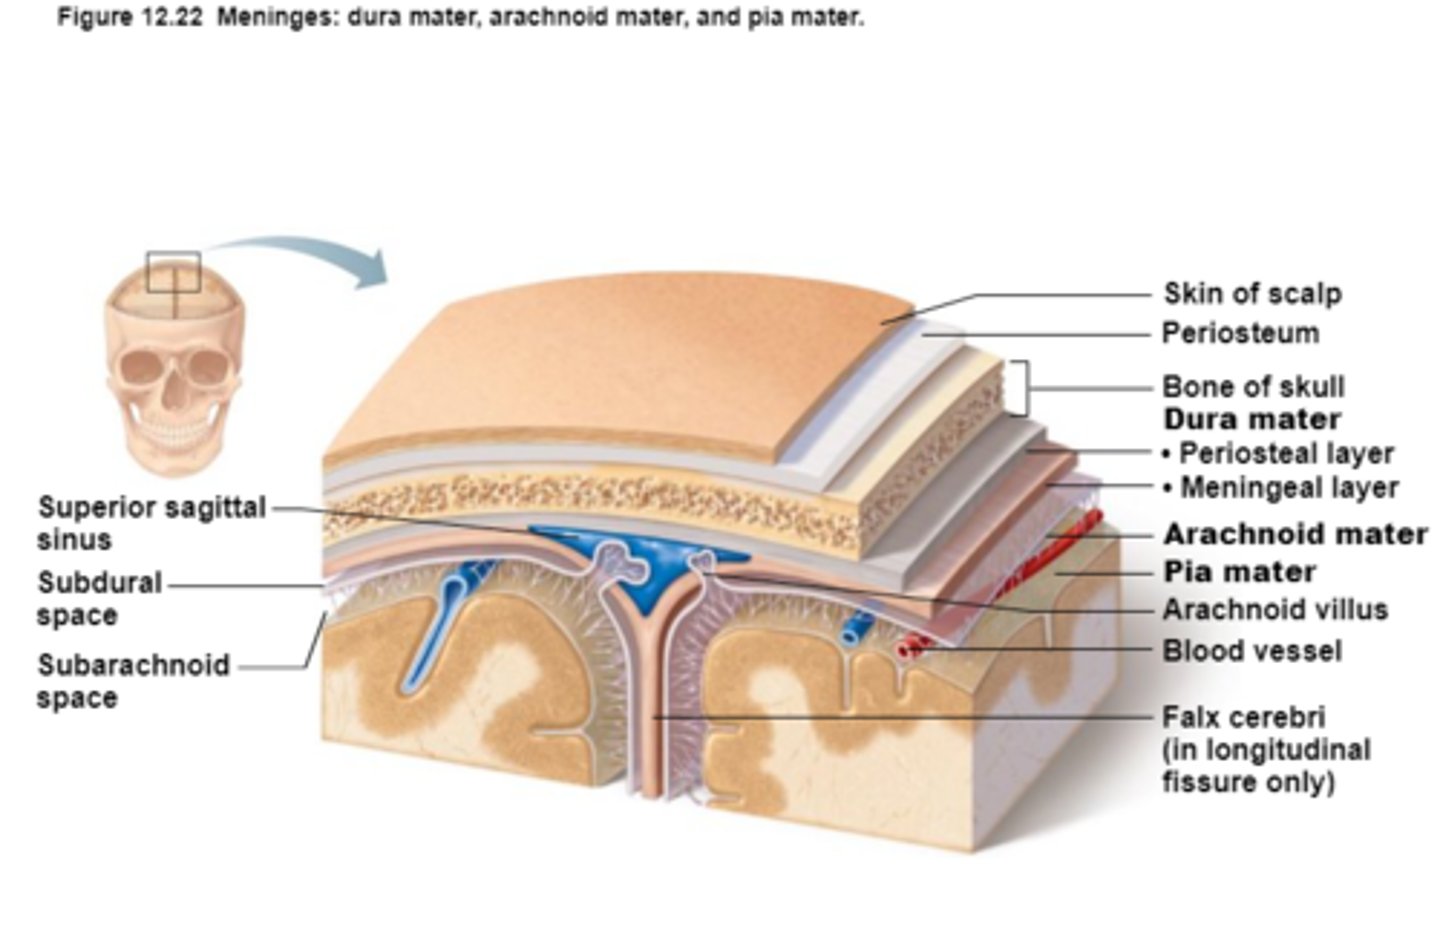

Protection of the CNS

1) scalp and skin

2) skull and vertebral column

3) meninges

Meninges

Connective tissue membranes that lie just external to the CNS organs that:

-Cover and protect the CNS

-Protect blood vessels and enclose venous sinuses

-Contain cerebrospinal fluid

3 Layers (external to internal) of Meninges

Dura Mater,

Arachnoid Mater,

Pia Mater

Dura Mater

First layer of Meninges,

Has layers that can separate to form dural sinuses:

-Periosteum

-Meningeal layer

Arachnoid Mater

Second layer of the Meninges,

Subarachnoid space with cerebrospinal fluid

Pia Mater

Third layer of Meninges

Dural Venous Sinuses

Blood and Cerebrospinal fluid (CSF) collection for return to circulatory vessels exiting skull